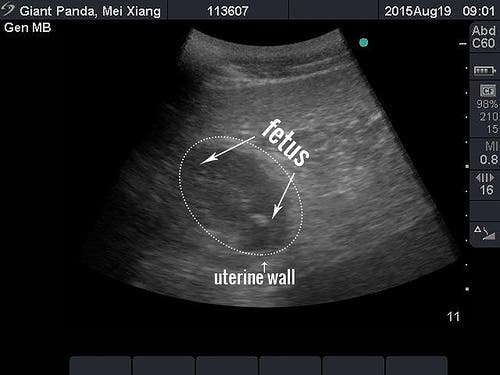

Sonogram Wednesday detects what zoo veterinarians believe is a developing giant panda fetus. Bao Bao could soon have another sibling.

For the first time at the zoo, veterinarians detected something new during an ultrasound procedure Wednesday morning, the zoo said in a news release. They said they believe it is a developing giant panda fetus.

Panda could give birth as early as next week

Based on the size of the fetus, which is about four centimeters, veterinarians estimate that Mei Xiang could give birth early next week, or possibly in early September. In past years, veterinarians have only detected changes to Mei Xiang’s uterus, which occurs for both a pregnancy and pseudopregnancy. Historically, and since Aug. 7 of this year, Mei Xiang declined participating in ultrasounds at this stage, so it was a surprise when she responded to the panda keepers’ calls this morning, the zoo said.

SONOGRAM of Mei Xiang on Wednesday morning courtesy of National Zoo